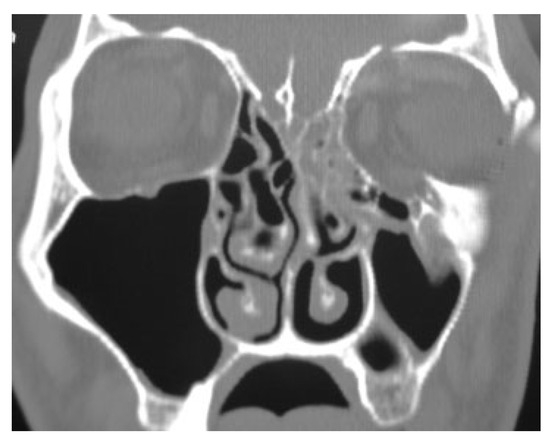

Pathologic Fractures in Bisphosphonate-Related Osteonecrosis of the Jaw—Review of the Literature and Review of Our Own Cases

Background Bisphosphonates are powerful drugs used for the management of osteoporosis and metastatic bone disease to avoid skeletal-related complications. Side effects are rare but potentially serious such as the bisphosphonate-related osteonecrosis...